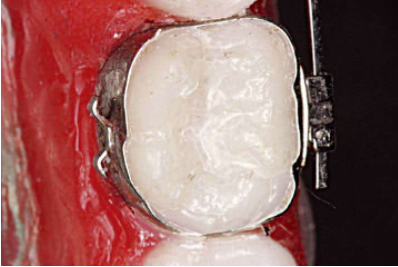

2、试带环的时候,不要选择过紧的带环,带环太小无法在磨牙牙冠上做调整;带环也不能太大,不要指望用粘结剂充填过大的带环和牙冠空间,过大的带环在矫治过程中很容易脱落。要保证带环的颊管位置应该在磨牙牙冠的临床冠中心,带环颊管的近中边缘应与磨牙的近中颊尖中央脊对齐,颊管与磨牙近远中颊尖连线平行(图7)。

3、颊面管的粘结定位为第一磨牙的颊面管应位于牙齿的临床冠中心,与磨牙近远中颊尖连线平行,上颌第二磨牙的颊面管位于临床冠中心偏颌方0.5mm。如此可以保存上颌磨牙后部的补偿曲线(图8,图9)。